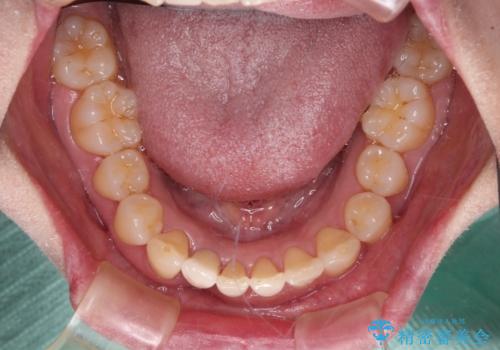

- 下顎前歯が抜けそうとのことで来院された患者様です。

初診の状態ではすぐにでも抜けそうな状態で、インプラントによる補綴治療を行うこととしました。

インプラント治療に際し、前歯の叢生に対する矯正治療を提案したところ、興味を持たれたので、インビザライン・ライトによる矯正治療を行うこととしました。

抜歯後にスペースができると恥ずかしいため、抜歯した歯を接着剤で固定した上で矯正治療を行い、その後インプラントやオールセラミッククラウンの装着を行うこととしました。